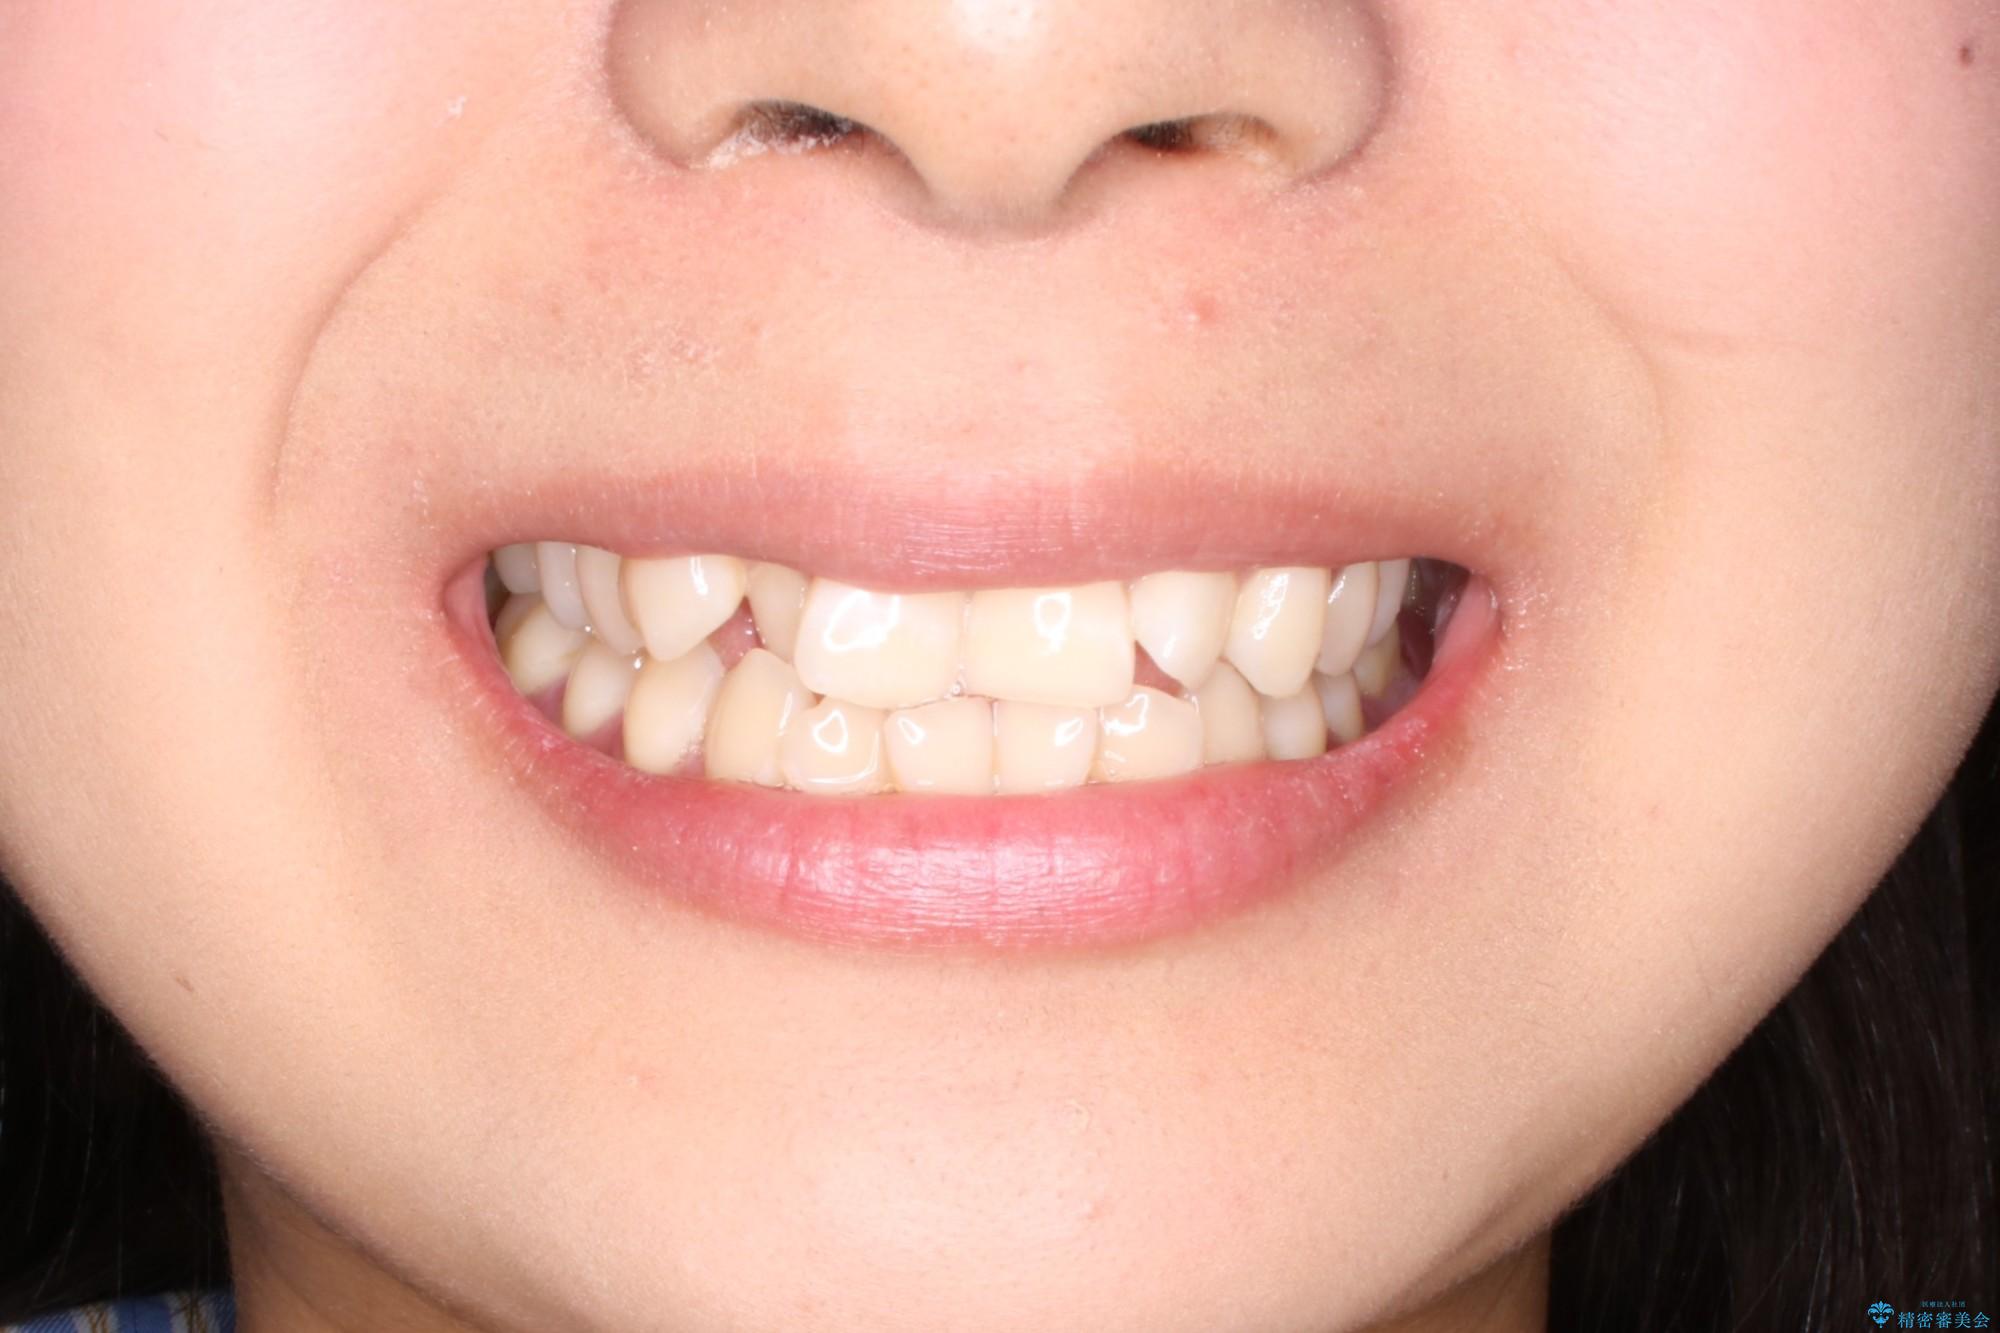

抜かない矯正 審美装置によるワイヤー治療

- 20代女性

- 前歯のガタガタを主訴に来院されました。

インビザラインも提案しましたが、装着時間を確実に確保できるか不安ということもありワイヤー矯正を希望されました。

装着時間に不安がある人は、ワイヤー矯正をおすすめしております。短期間で治療でき患者様にも満足していただきました。